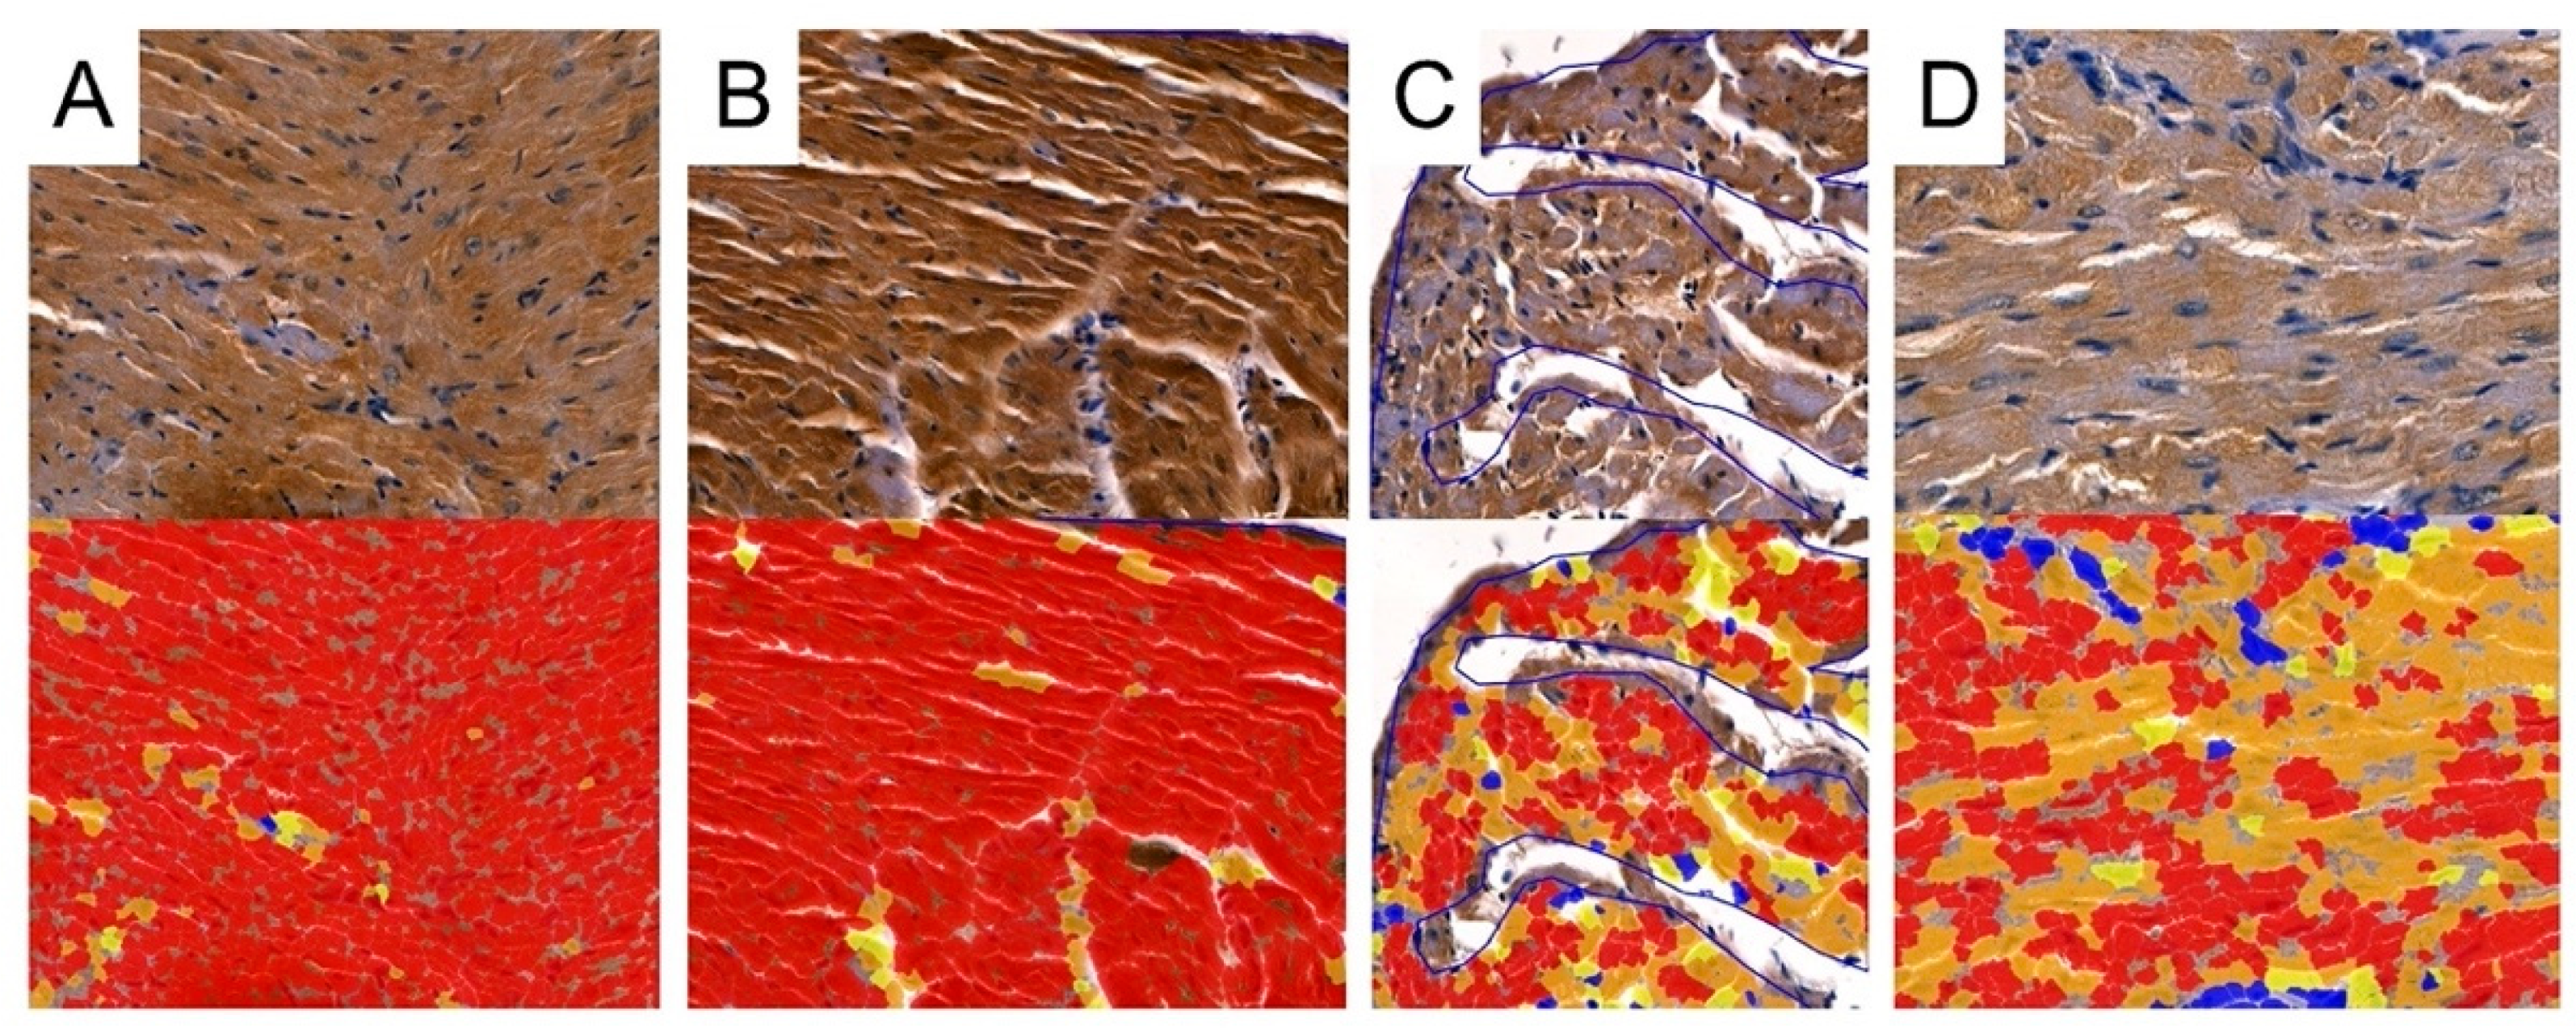

3.5. Digital Analysis of Immunolocalization of the MMP-2/TIMP-2

3.6. Digital Analysis of Immunolocalization of the MMP-9/TIMP-1